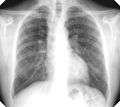

For uncomplicated silicosis, chest x-ray will confirm the presence of small (< 10 mm) nodules in the lungs, especially in the upper lung zones. Using the ILO classification system, these are of profusion 1/0 or greater and shape/size "p", "q", or "r". Lung zone involvement and profusion increases with disease progression. In advanced cases of silicosis, large opacity (> 1 cm) occurs from coalescence of small opacities, particularly in the upper lung zones. With retraction of the lung tissue, there is compensatory emphysema. Enlargement of the hilum is common with chronic and accelerated silicosis. In about 5-10% of cases, the nodes will calcify circumferentially, producing so-called "eggshell" calcification. This finding is not pathognomonic (diagnostic) of silicosis. In some cases, the pulmonary nodules may also become calcified.

Chest X-ray showing uncomplicated silicosis

Complicated silicosis

Silicosis ILO Classification 2-2 R-R